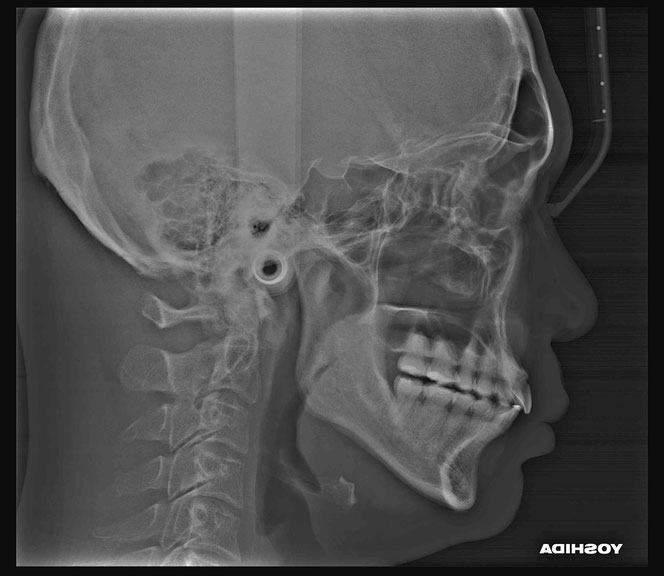

治療後の変化

再生治療により、

2~3ミリ下がっていた歯ぐきが回復。

歯の長さが自然なバランスに戻り、

厚みのある丈夫な歯ぐきが再建されました。

奥歯6本の再生治療を行ったケースでは、

虫歯予防という機能面の改善も期待できます。